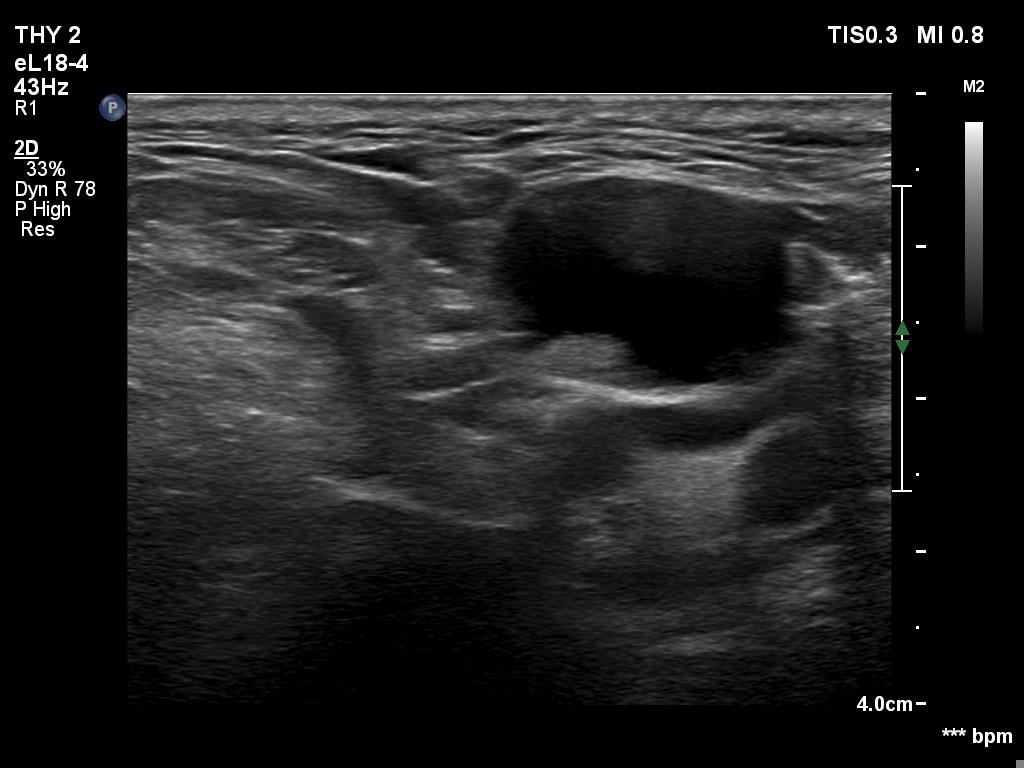

Ultrasonography. The right lobe was echonormal and intact. A large mass occupied almost the entire left lobe. On this side, normal thyroid tissue could only be identified in the dorsal part. The mass was composed of echonormal and hypoechoic areas, had macrocalcifications, irregular intranodular vascularity and proved to be very hard on elastography. There were multiple lymph nodes in III, IV and V left neck compartments. One of the nodes was in close proximity to the jugular vein and was suspicious of having broken into the vessel. The trachea was significantly narrowed at the lower level of the thyroid.

2. There are several remarkable findings in this case, e.g., the destruction of the left lobe by the tumor, the elastography pattern, the relation of the largest metastatic lymph node and the jugular vein, the ultrasound demonstration of the trachea' stricture.